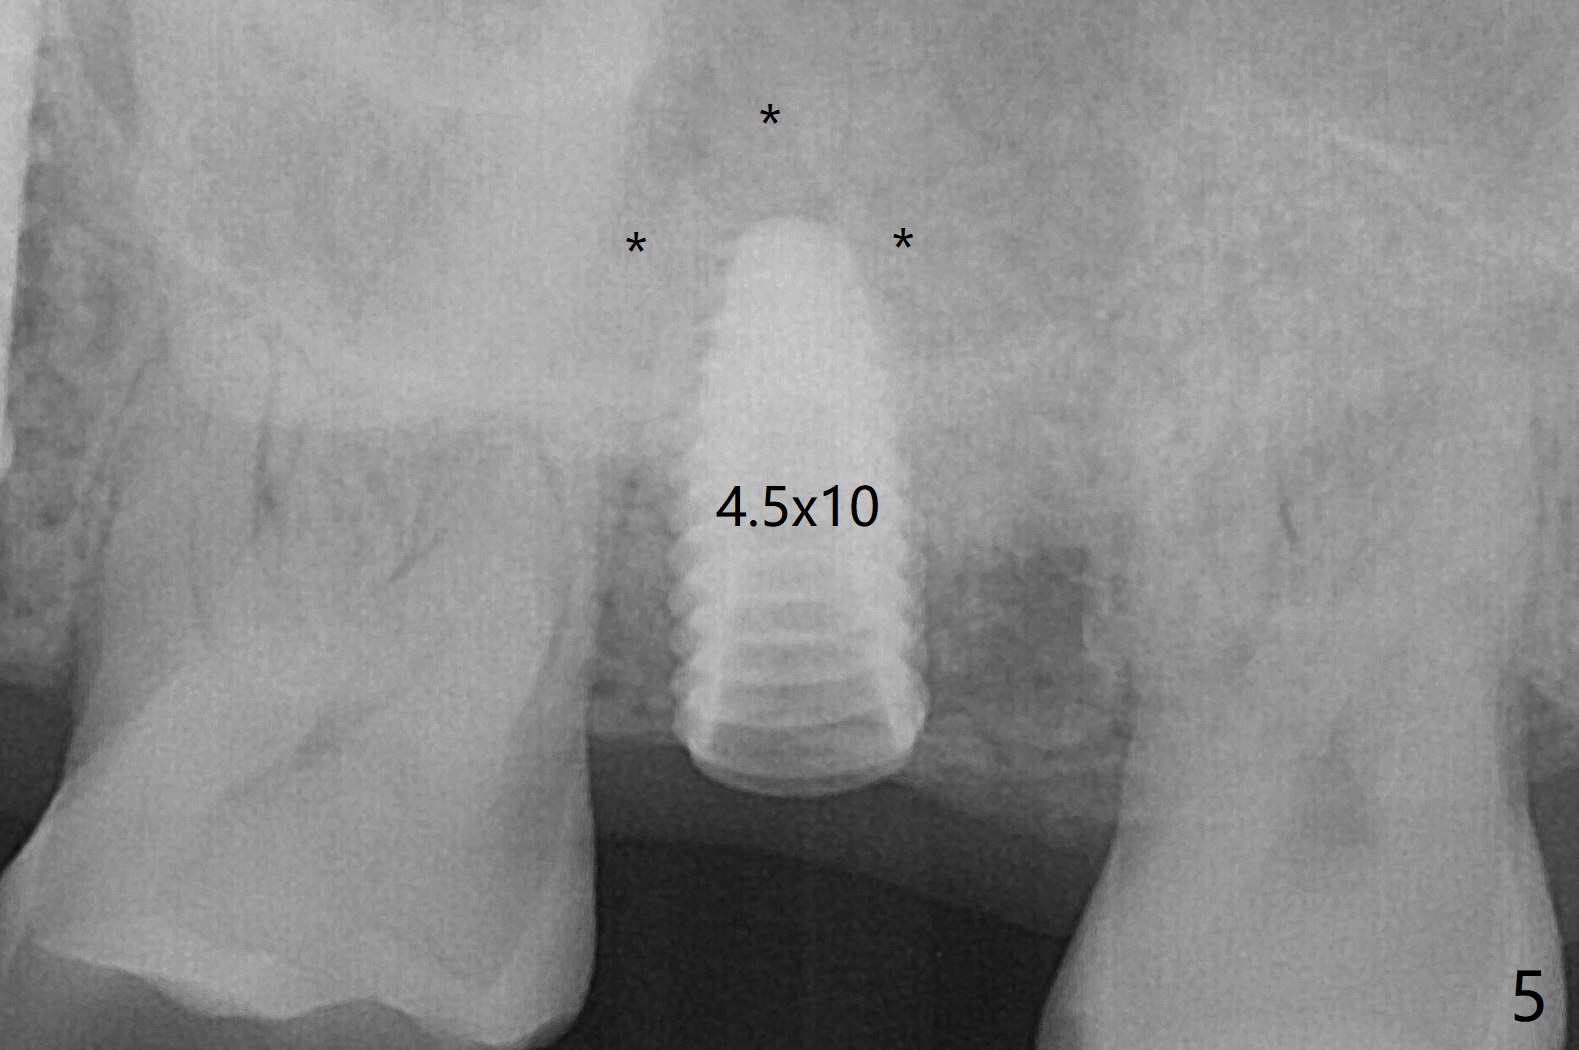

66岁男右上,左上7导板延期种植(足够角化龈,使用环形切刀),都提升,但是前者未植骨(图一,二(骨高度多,进入上颌窦少)),后者植骨(图六(*),七),由于扭力低(小于15Ncm),放置愈合螺帽和剪成圆形六个月胶原膜,使用牙周胶水(图三,八),之后不再放置牙周敷料。当钻头接近左侧上颌窦底板时,放置骨粉(图四-六:*),使用报废植体(图四,五)和正式植体(图六)将骨粉推入上颌窦。术后病人抱怨食物撞击伤口疼痛,即刻修复减少术后疼痛。术后5个月没有骨质吸收,基台完全就位(图十一,二)。